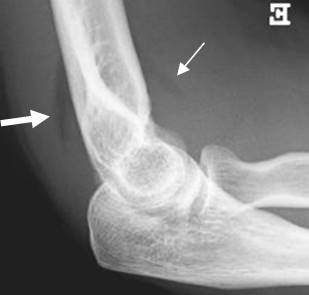

Fig 155. Derrame articular.

A: Rx lateral. Visualización del cojinete graso anterior normal (Flecha delgada) y el posterior, siempre patológico, que indica derrame articular. (Flecha gruesa).